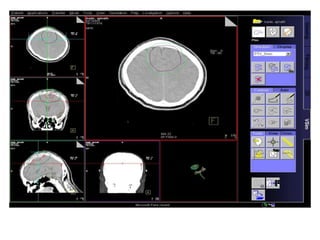

RT planning: meningioma

GTV/CTV = residual tumour / tumour bed for gr II / gr III

CTV = 5 mm for benign meningiomas

2 - 3 cms for high grade meningiomas / HPC

PTV = 2mm for SRT

5mm for 3DCRT

All normal structures contoured

Dosage:

Gr-I:

54Gy/30# conformal RT

25Gy/5# / 13Gy/1#

Gr II & III meningioma:

60Gy/30#/6wks

Conformal RT

Grade I Grade II/III

Tharmoplastic mask

CT scan with contrast- 3 mm slice

MRI scan with T1 contrast & T2 flair is a must

RT planning: meningioma GTV/CTV= residual tumour / tumour bed for gr II / gr III CTV = 5 mm for benign meningiomas 2 - 3 cms for high grade meningiomas / HPC PTV = 2mm for SRT 5mm for 3DCRT All normal structures contoured Dosage: Gr-I: 54Gy/30# conformal RT 25Gy/5# / 13Gy/1# Gr II & III meningioma: 60Gy/30#/6wks Conformal RT Grade I Grade II/III Tharmoplastic mask CT scan with contrast- 3 mm slice MRI scan with T1 contrast & T2 flair is a must